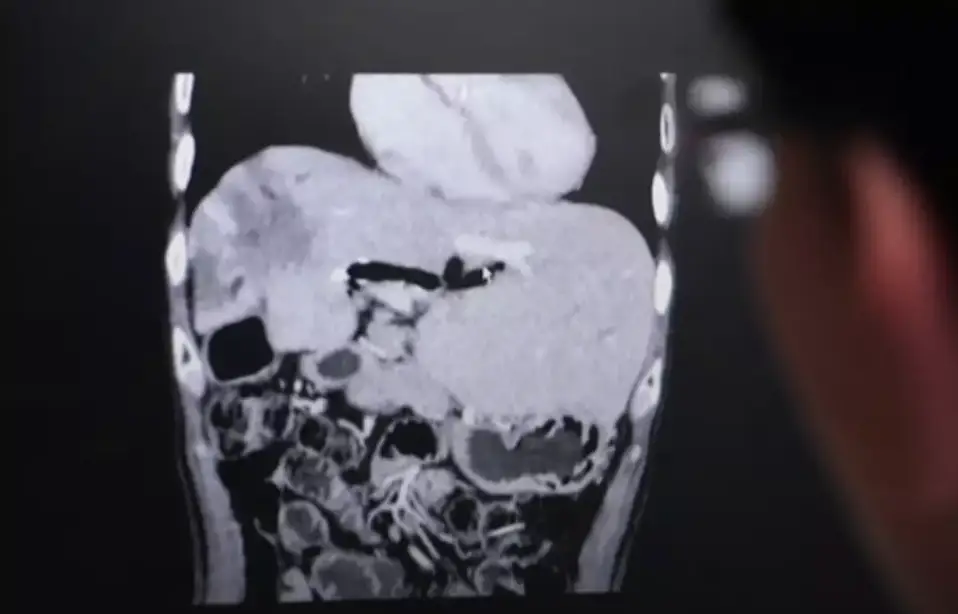

X-ray explained

An x-ray of someone's body who had eaten koi pla was previously released to the public, showing the parasite in their digestive system.

From here, it can end up killing the individual, in what is a very big threat to life among these communities.